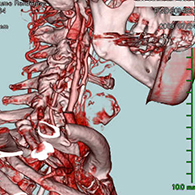

<手術中の脳血管撮影画像>

瘤(こぶ)は消失

<画像所見>

左眼の奥に大きな動脈瘤認める。

(→動脈瘤)